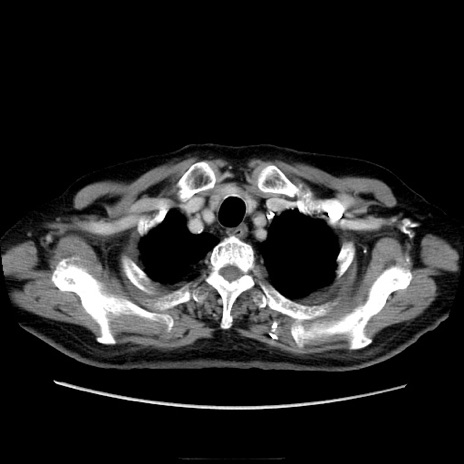

症例21(横断像)

【症例】70歳代男性

【主訴】腹痛

【現病歴】肝硬変・肝細胞癌にてかかりつけの方。約9時間前に食後より腹痛出現。症状が徐々に増悪し、嘔吐出現したため来院。

【既往歴】肝硬変、肝細胞癌(RFA、TACE後)

【身体所見】意識清明、表情苦悶様、BT 36℃、BP 129/78mmHg、P 88bpm、SpO2 97%(RA)、右上腹部から心窩部にかけて圧痛あり、反跳痛なし、筋性防御あり。

【データ】WBC 5800、CRP 0.16